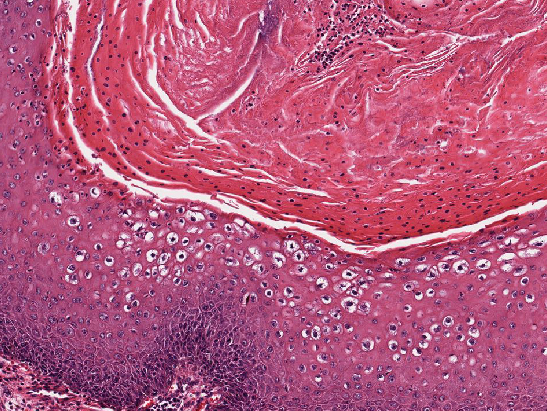

Microscopic (histologic) description

- Resembles condyloma acuminatum

- Diagnostic criteria

- Well formed papillae with a prominent central fibrovascular core

- Hyperkeratosis with parakeratosis and marked acanthosis

- Koilocytes on upper third of the squamous epithelium

- Chronic inflammatory infiltration

- Local extension and displacement of surrounding tissues but no evidence of dysplasia / invasion (WHO Classification of Tumours Editorial Board: Digestive System Tumours, 5th Edition, 2019)

- Low mitotic rate, usually confined to the basal layer with no abnormal mitoses (Histopathology 2017;70:938)

- About 30 - 35% may develop an invasive component; especially in high risk HPV positive cases (Virchows Arch 2020;476:543, Dis Colon Rectum 1989;32:481)

Microscopic (histologic) images